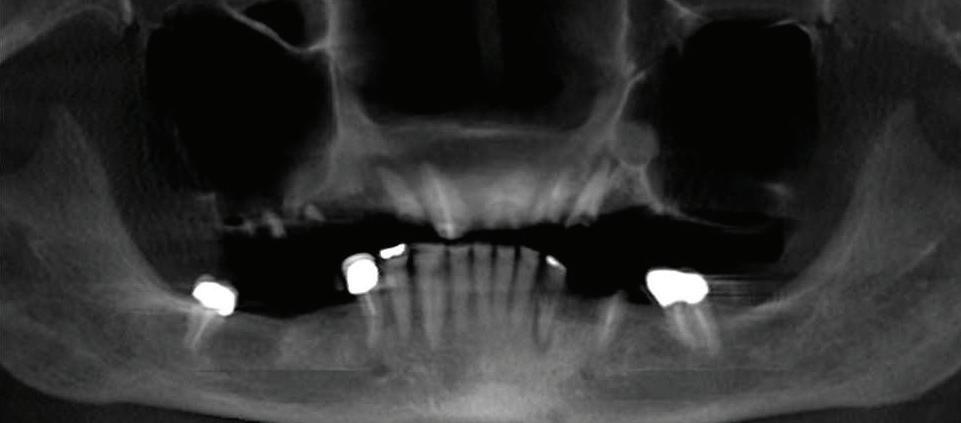

Submitted By Sivakumar Sreenivasan, DMD, MDS

Dental Implant Center of Rockville

Can just four implants replace all of the teeth on the top or the bottom of your mouth? Thanks to advances in dental implant technology, that answer is a resounding yes.

Believe it or not, tooth loss is extremely common among adults, especially as we age. In fact, more than 35 million people in America are missing all of their upper and/or lower teeth. Rather than living with the discomfort and hassles of dentures, many people are opting for what is called “all-onfour” dental implant restoration.

To fully understand this remark-

able technique for replacing teeth, you should first understand what a dental implant is. An implant is a small titanium screw that fits inside your jawbone and replaces the root-part of a missing tooth. Minor surgery is required to insert the implants. Once the implant is in place, a crown is attached to give you a highly realistic-looking and functional prosthetic tooth.

Here’s where it gets really interesting: You do not need a dental implant for each and every one of your missing teeth. All you need is four precisely placed implants on the top of your mouth, and four on the bottom, to restore your full smile. That’s the beauty of the all-on-four. And because the implant is made of titanium, it has the unique ability to fuse to living bone and function as part of it. So eventually, the dental implant becomes part of the jawbone and serves as a strong, long-lasting foundation for your new teeth.

Besides ensuring that your implants are permanently fixed in place,

this bone fusion has another important benefit: it prevents future bone loss in the jaw. This helps to maintain a more youthful facial structure – and better oral health. But perhaps the biggest surprise about the all-on-four is how quickly it can transform your life.

insert the titanium screws into your jawbone. Most likely, they will place two implants toward the front of your mouth and two towards the back of your mouth so the “anchors” can evenly bare the force of the denture.

How Do You Know If The All-On-Four Procedure Is The Right Option For You?

At your All-On-Four consultation, you’ll receive a 3D CT Scan. This scan will help determine if you need implants and assist your doctors in creating your treatment plan. So if you want to learn more about dental implants, simply schedule a consultation with an All-On-Four provider. It’s the best way to find out how dental implants can change your life.